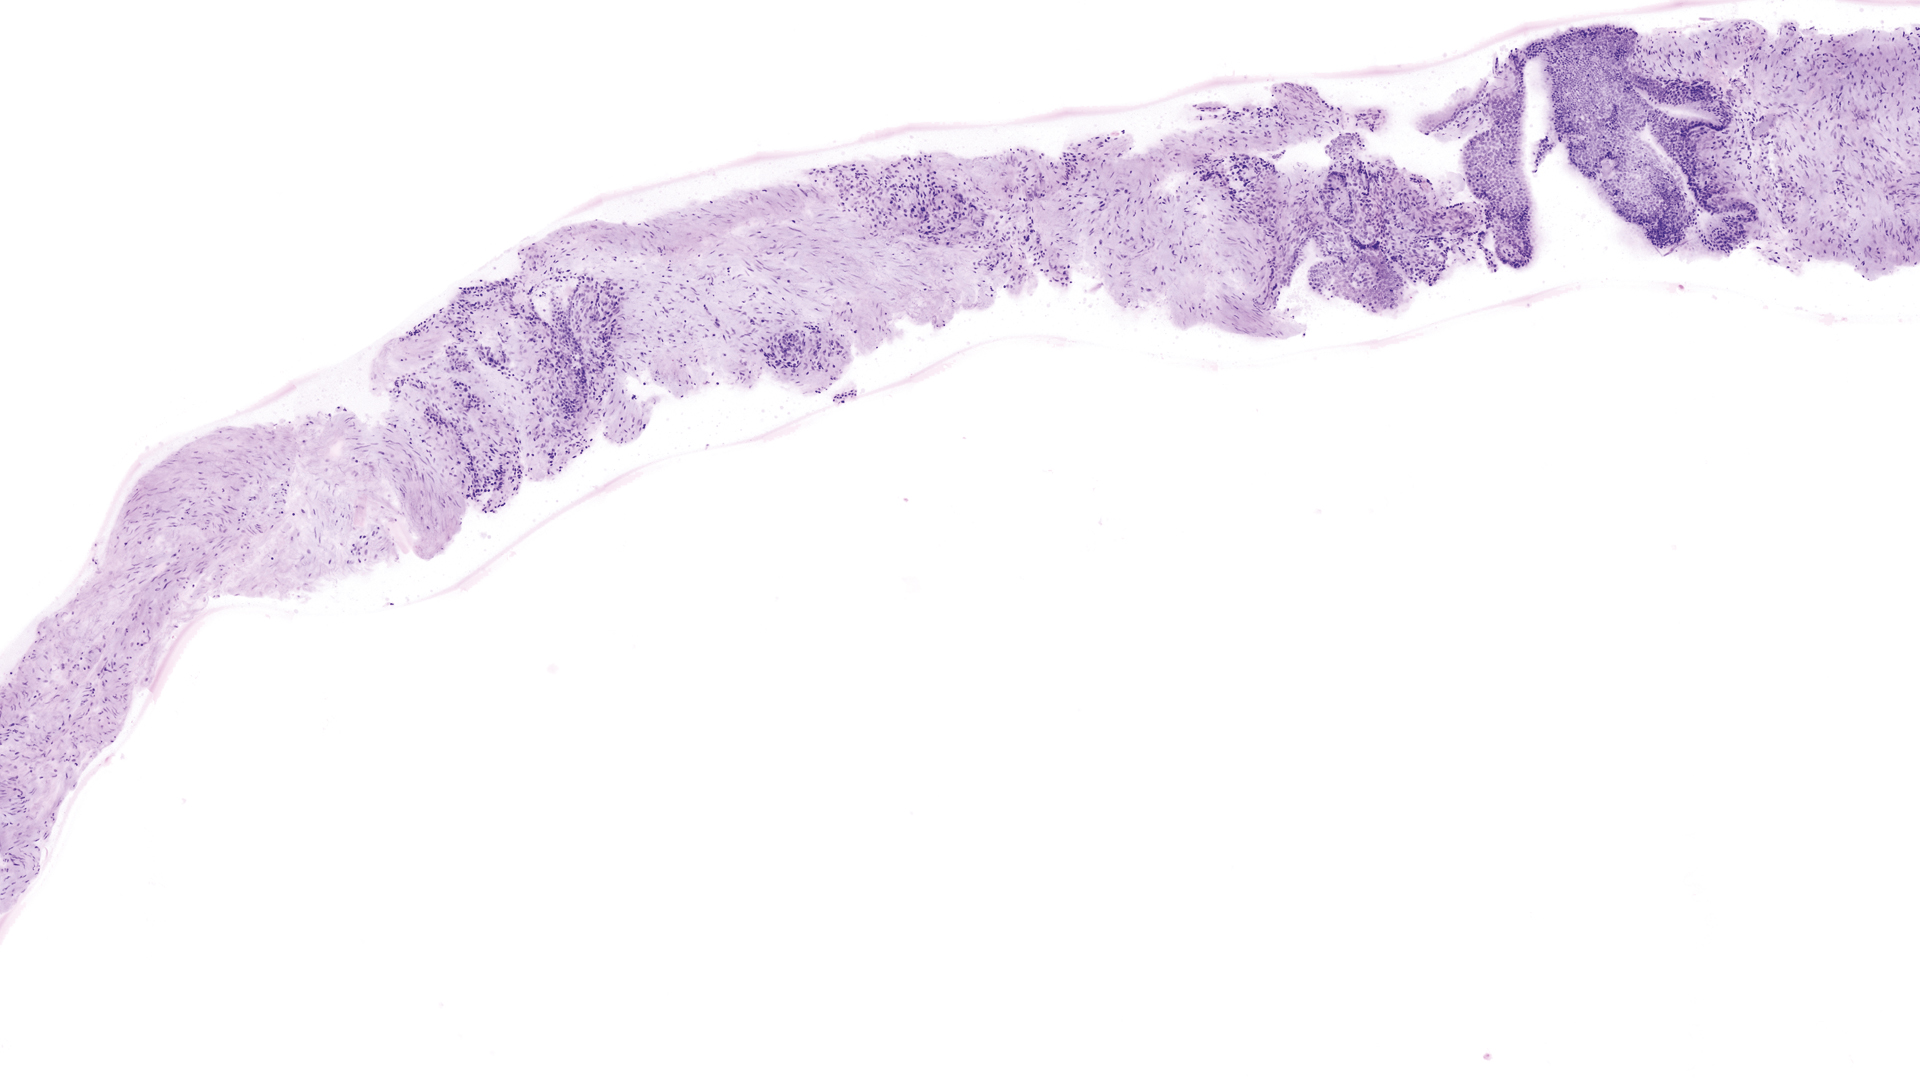

2. Intraoperative margin control

The VivaScope 2500 technology offers many advantages over frozen section analysis for microscopically controlled surgery. The time needed to complete a surgery can be reduced significantly. Integrated into a surgical workflow, VivaScope scans provide information comparable to H&E images derived from FFPE or frozen sections. The examination can be performed without a laboratory.

Image courtesy of Dr. Anna Crescenzi, University Hospital Campus Bio-Medico, Rome

VivaScope 2500 confocal image example 3